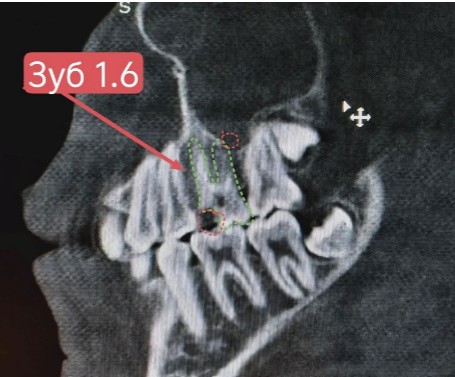

Проведена компьютерная томография околоносовых пазух, которая подтвердила наличие правостороннего гемисинусита (воспаление нескольких пазух с одной стороны), как следствие периодонтита зуба 1.6.

На снимке детально представлена область пораженного зуба 1.6.